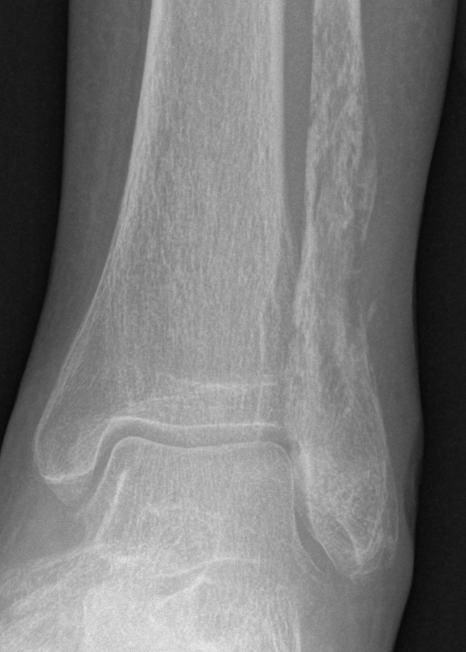

Osteosarcoma of the humerus Osteosarcoma of the fibula